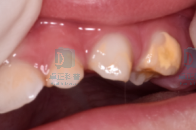

2

牙本质发育不全;

图片

牙本质发育不全是一种遗传性疾病,典型表现是牙齿呈琥珀色,容易出现广泛的磨耗、釉质剥脱,继而引起牙髓根尖周病变,因此早期发现、早期保护至关重要。如果发现孩子牙齿呈现出这种琥珀色改变,应尽早寻求专业儿童牙医的帮助。